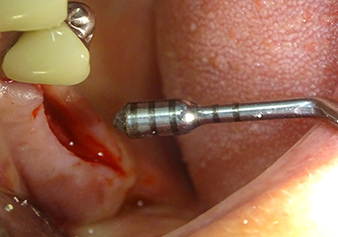

L’insert I2A (diamètre 2,0 mm) est ensuite utilisé pour perforer le plancher sinusien par intermittence et à la plus petite échelle possible. Cette méthode piézochirurgicale spéciale garantit que la membrane de Schneider n’est pas endommagée. Quand le Z25P est utilisé, la membrane est déjà légèrement relevée sous l’effet du fluide de refroidissement délivré via la pointe de l’insert (Fig. 3). Seulement 50 % du fluide de refroidissement sont éjectés afin d'éviter une pression élevée sur le site implantaire.